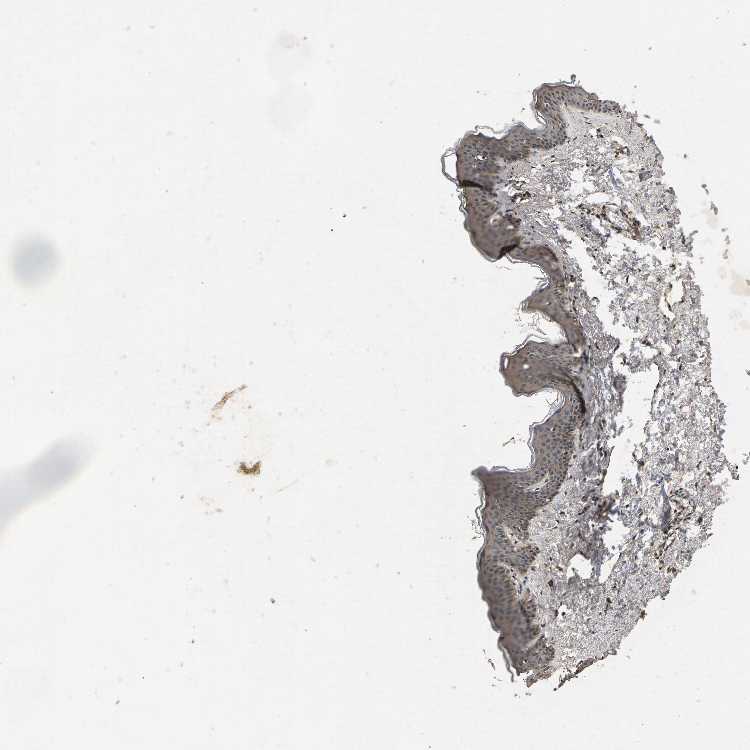

SKIN 2 - Antibody stainingi

Antibody staining in the annotated cell types in the current human tissue is reported as not detected, low, medium, or high, based on conventional immunohistochemistry profiling in selected tissues. This score is based on the combination of the staining intensity and fraction of stained cells.

Each image is clickable and will lead to virtual microscopy that enables deeper exploration of all samples and also displays staining intensity scores, fraction scores and subcellular localization as well as patient and tissue information for each sample.

Antibody CAB022645

Epidermal cells Not detected